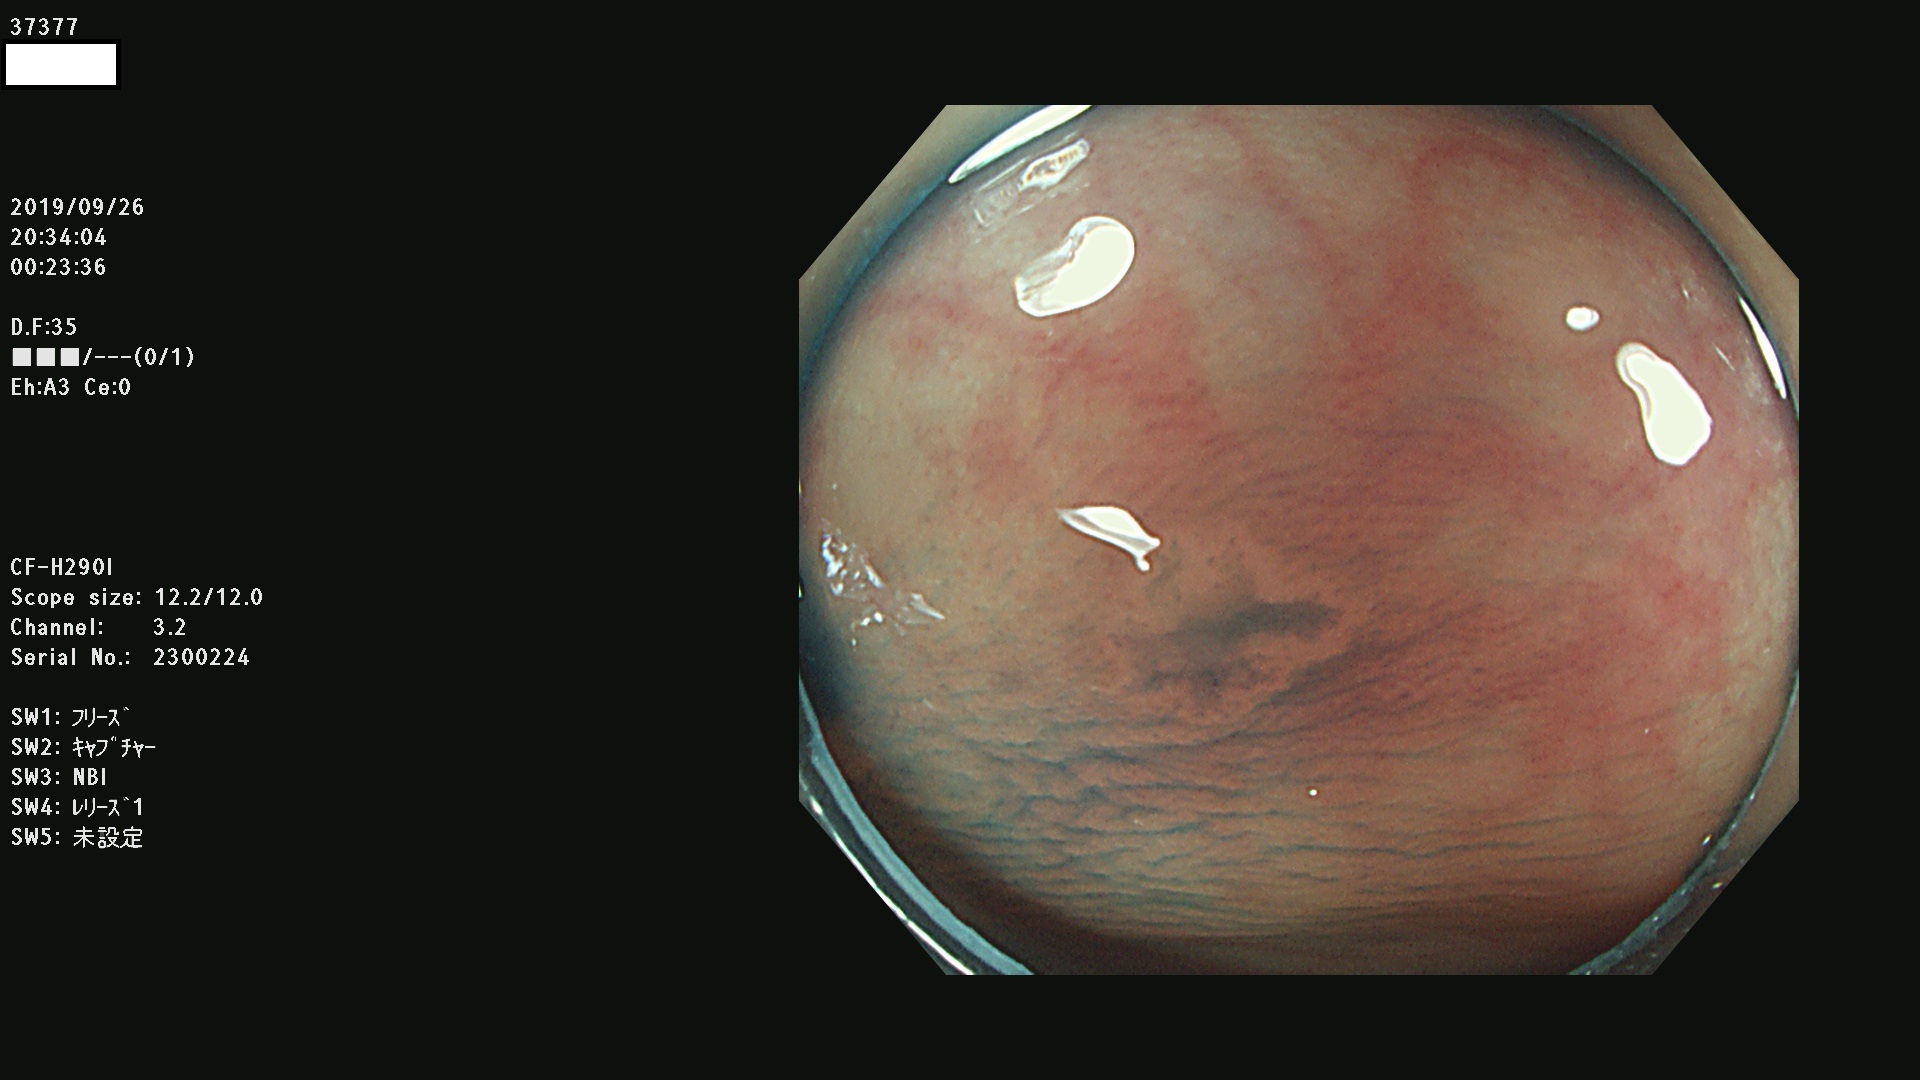

37300(SSAPのみ) 37301 37303 37304 37306 37307 37308 37309 37312 37313 37315(SSAPのみ) 37316 37317(SSAPのみ) 37319 37321(SSAPのみ) 37322 37323 37324 37325 37326 37328(SSAPのみ) 37329 37330 37331 37332(SSAPのみ) 37333 37334 37336 37337 37338 37340 37342 37343(SSAPのみ) 37344 37345 37346 37347 37348 37352(SSAPのみ) 37353 37354 37355 37356 37358 37360 37361(SSAPのみ) 37362 37363 37366 37367 37369 37370 37371 37372(SSAPのみ) 37375 37376 37377 37380 37381(SSAPのみ) 37382 37383 37384 37385(SSAPのみ) 37386 37387 37388 37389 37390 37392(SSAPのみ) 37393 37394 37395 37396(SSAPのみ) 37397 37398(SSAPのみ) 37399

発見困難で危険性の高い平坦型病変(上記100名より抽出) )